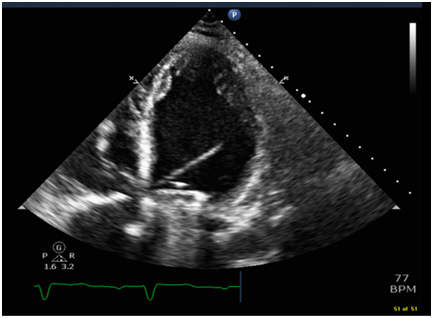

57- year-old women underwent 2 vessel coronary artery bypass grafting (CABG), Mechanical mitral valve replacement and tricuspid valve repair. She required a chest drain insertion for worsening left sided pleural effusion this was done in the surgical intensive care unit using a 12 F pig tail. Shortly following the insertion she started to become breathless and hemodynamically compromised with a drop of her blood pressure and oxygen saturation. It was noted that the chest drain was draining frank blood which was clamped. Chest x-ray revealed an abnormal position of the drain across the heart (Figure 1). Bed side echocardiogram showed the drain traversing the left ventricle (Figure 2). Bubble study through the chest drain showed contrast bubbles inside the left ventricle confirming position of the drain and perforation of the left ventricle (Figure 3). The drain was kept in situ. She was taken to the operating theatre for an emergency left thoracotomy. It appeared that the drain was penetrating the left lung and the left ventricle (Figure 4).

Figure 2 Arrow points to the chest tube drain traversing the left ventricle.

Figure 3 Bubbles inside the left ventricle to ascertain position of the chest drain.

It was proposed that the safest way to place a small-sized chest drain correctly is by using image guidance by ultrasound or computed tomography. If however the heart is perforated, the drain must be clamped and computed tomography be obtained immediately as long as the patient is in a stable hemodynamic condition. If the patient is hemodynamically unstable then a transthoracic echocardiography with contrast would be great diagnostic modality as in this situation by demonstration of “bubbles” in the perforated cardiac chamber following agitated saline injection through the chest drain. Emergency thoracotomy is the treatment of choice in this type of complication.